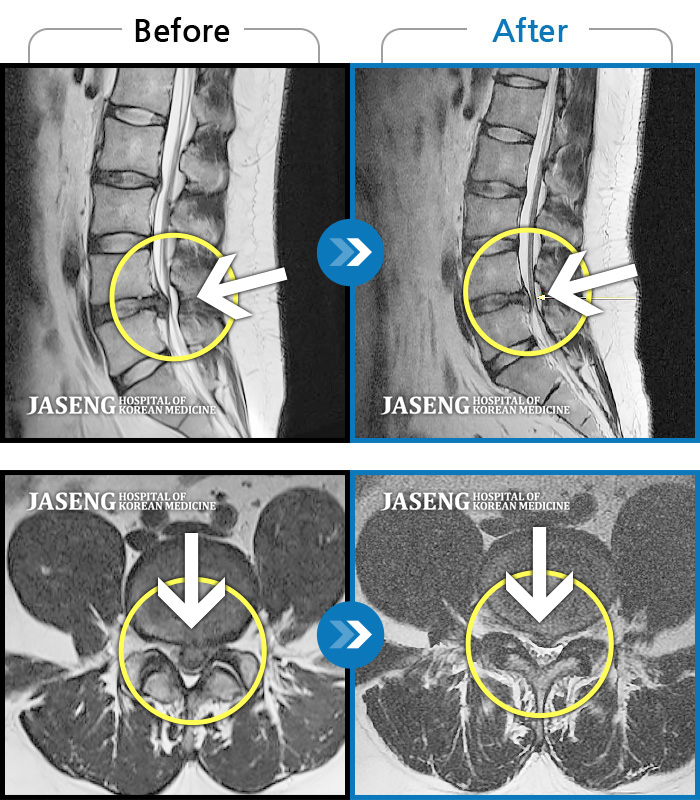

Before

After

환자에게 사전 동의를 받아 동일 조건에서 촬영되었습니다.

개인에 따라 치료 후 부작용이 발생할 수 있으니 의료진과 상담 후 치료를 진행하시기 바랍니다.

허리 통증과 좌측 둔부 및 하지 방사통 극심하여 일상생활 불가 및 눕기도 힘든 상태로 내원